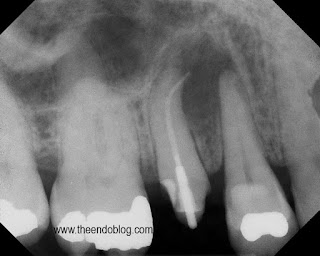

This root canal was done by her general dentist 3 months earlier.  As you can see it is overfilled, post placed, crown prepped and ready for new crown, but patient continues to have symptoms with the tooth.

CBCT taken to evaluate the root morphology. It is clear that this is a single root/canal.  (The canal has an oblong shape)  It was chosen to treat this tooth with apical surgery to preserve the restorative work that has been completed and assure that the overextened gutta percha is removed.